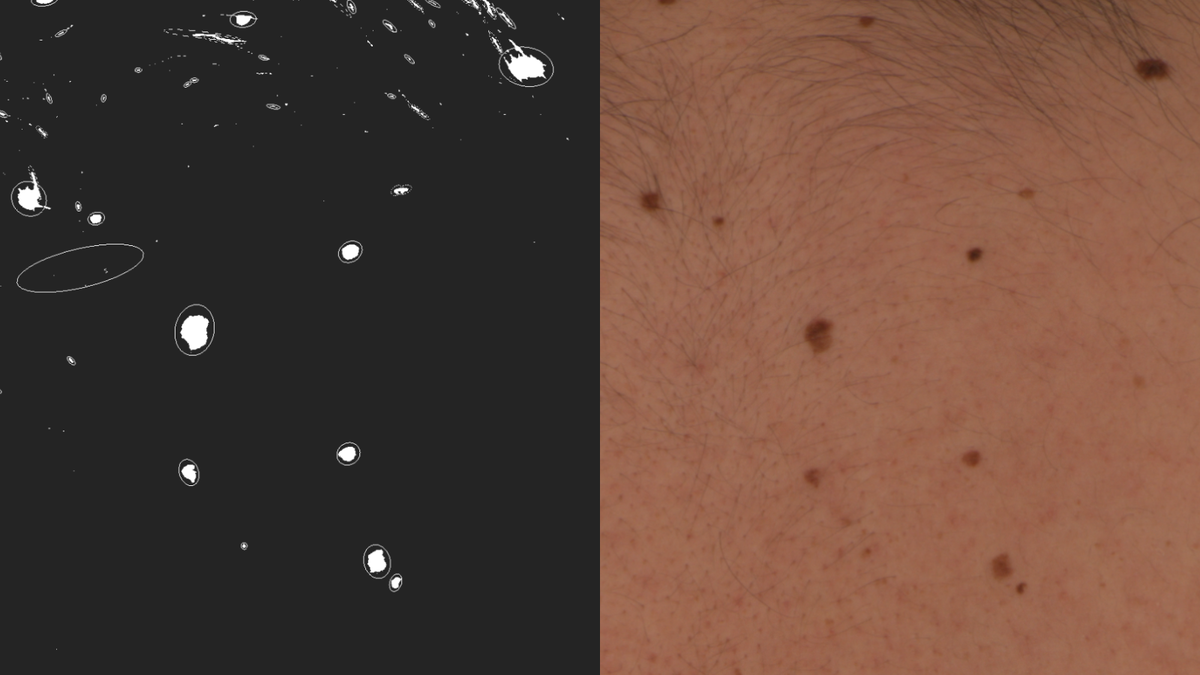

Родинки, которые меняются медленно и незаметно: как не пропустить «тихую» угрозу

Большинство из нас знает, что если родинка внезапно почернела или начала кровоточить — нужно бежать к врачу. Но самая коварная форма рака кожи — меланома — часто ведет себя иначе. Она может маскироваться под обычное пятнышко, которое меняется годами: на долю миллиметра вширь, на едва заметный тон в цвете. В 2026 году онкодерматологи призывают к «медленной настороженности». Мозг склонен привыкать к тому, что мы видим в зеркале каждый день, и игнорировать микроскопические сдвиги. В этой статье мы разберем, как обнаружить эволюцию родинки, которую не фиксирует глаз, почему «гадкий утенок» на теле — это плохой знак и как современные технологии помогают увидеть болезнь задолго до её агрессивной стадии.

5 признаков «ленивой» трансформации родинки

2. Размытие границ (Эффект акварели)

Здоровая родинка обычно имеет четкий край. Медленное изменение часто проявляется в том, что одна сторона пятна начинает «растекаться», становясь похожей на след от капли акварельной краски на влажной бумаге.

3. Многоцветие внутри одного пятна

В норме родинка должна быть однородной.

Тревожный знак: Появление внутри старой родинки крошечных вкраплений другого цвета: черного, серого, розового или даже белого (зоны самопроизвольного регресса). Это говорит о том, что внутри невуса происходят разные биологические процессы.

4. Исчезновение кожного рисунка

Посмотрите на родинку через лупу или при ярком свете. На здоровой коже видны бороздки и линии. Если поверхность родинки стала идеально гладкой, «лаковой» или на ней перестали расти волосы, которые были там годами — это признак того, что новые клетки разрушили нормальную архитектуру кожи.

5. Цифровая дерматоскопия. Раз в год посещайте врача, который делает «паспорт кожи». В 2026 году ИИ-алгоритмы способны сравнить снимки и заметить изменение в 0.1 мм, которое пропустит даже опытный глаз.